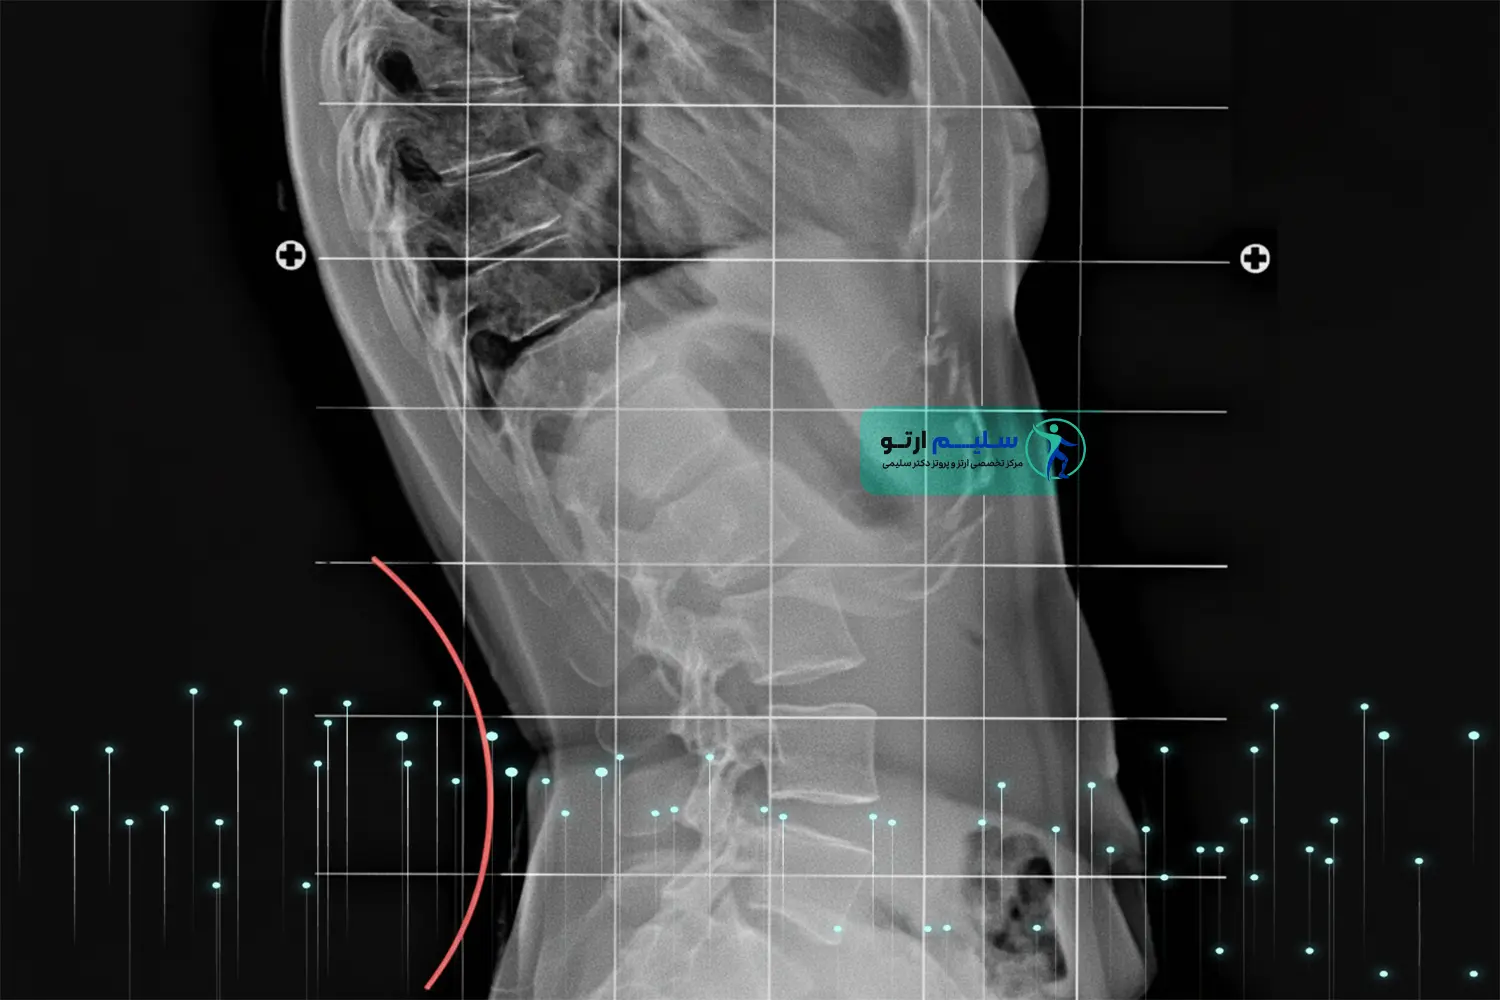

ستون فقرات ما، شاهکار مهندسی بدن انسان، دارای انحناهایی طبیعی است که وظیفه توزیع بار، جذب شوک و حفظ تعادل را بر عهده دارند . یکی از این انحناها، انحنای ناحیه کمری است که به آن لوردوز (Lordosis) گفته می شود .

لوردوز به خودی خود یک بیماری نیست؛ بلکه بخشی ضروری از ساختار آناتومیک ماست. اما وقتی این انحنا از حد طبیعی فراتر رود، وضعیتی به نام هیپرلوردوزیس یا همان گودی کمر بیش از حد به وجود می آید. این عارضه نه تنها ظاهر فیزیکی فرد را تحت تأثیر قرار می دهد، بلکه عامل اصلی درد مزمن کمر، فشار بر مفاصل فاست، و درگیری های عصبی جدی است.

هیپرلوردوزیس وضعیتی است که در آن زاویه انحنای ستون فقرات کمری به سمت داخل (قدامی) از محدوده طبیعی تجاوز می کند. محدوده طبیعی لوردوز کمری معمولاً بین ۲۰ تا ۴۵ درجه متغیر است . وقتی این زاویه به بیش از ۵۰ یا ۶۰ درجه می رسد، فشار غیرطبیعی بر دیسک ها، لیگامان ها و عضلات اطراف وارد شده و منجر به درد و اختلال عملکرد می گردد .

توجه تخصصی: لوردوز پاتولوژیک اغلب با کج شدن لگن به سمت جلو (Anterior Pelvic Tilt) همراه است. این تغییر وضعیت لگن،هسته اصلی مشکل است که توسط تیم ارتوپدی فنی ما باید تصحیح شود.

- آنالیز تصویربرداری (Imaging Analysis): بررسی عکس های رادیوگرافی (X-Ray) ایستاده برای اندازه گیری دقیق زاویه لوردوز کمری (مثلاً زاویه Cobb). این مهم ترین گام برای تعیین شدت عارضه و نیاز به ارتز است .